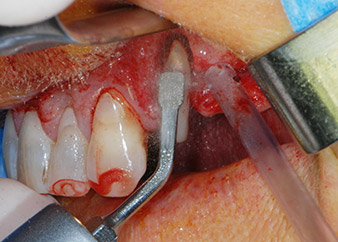

Vor der Insertion der Implantate wurde infiziertes Weichgewebe im Implantationsbereich und um das Abutment mit einem Instrument entfernt, das laut Hersteller primär zur Knochenbearbeitung und zum Sammeln von Knochenspänen vorgesehen ist (Piezomed, Einsatz B5) (Abb. 6 und 7).

piezochirurgisches Instrument

Abb. 6: Der Operationsbereich wird dann mit einem schabenden piezochirurgischen Instrument gereinigt.

Knochendefizite

Abb. 7: Nach dem Debridement sind die Knochendefizite an Zahn 27 mesial und um die Wurzel von Zahn 24 deutlich sichtbar.